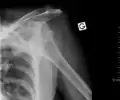

| Anterior dislocation of the left shoulder. | |